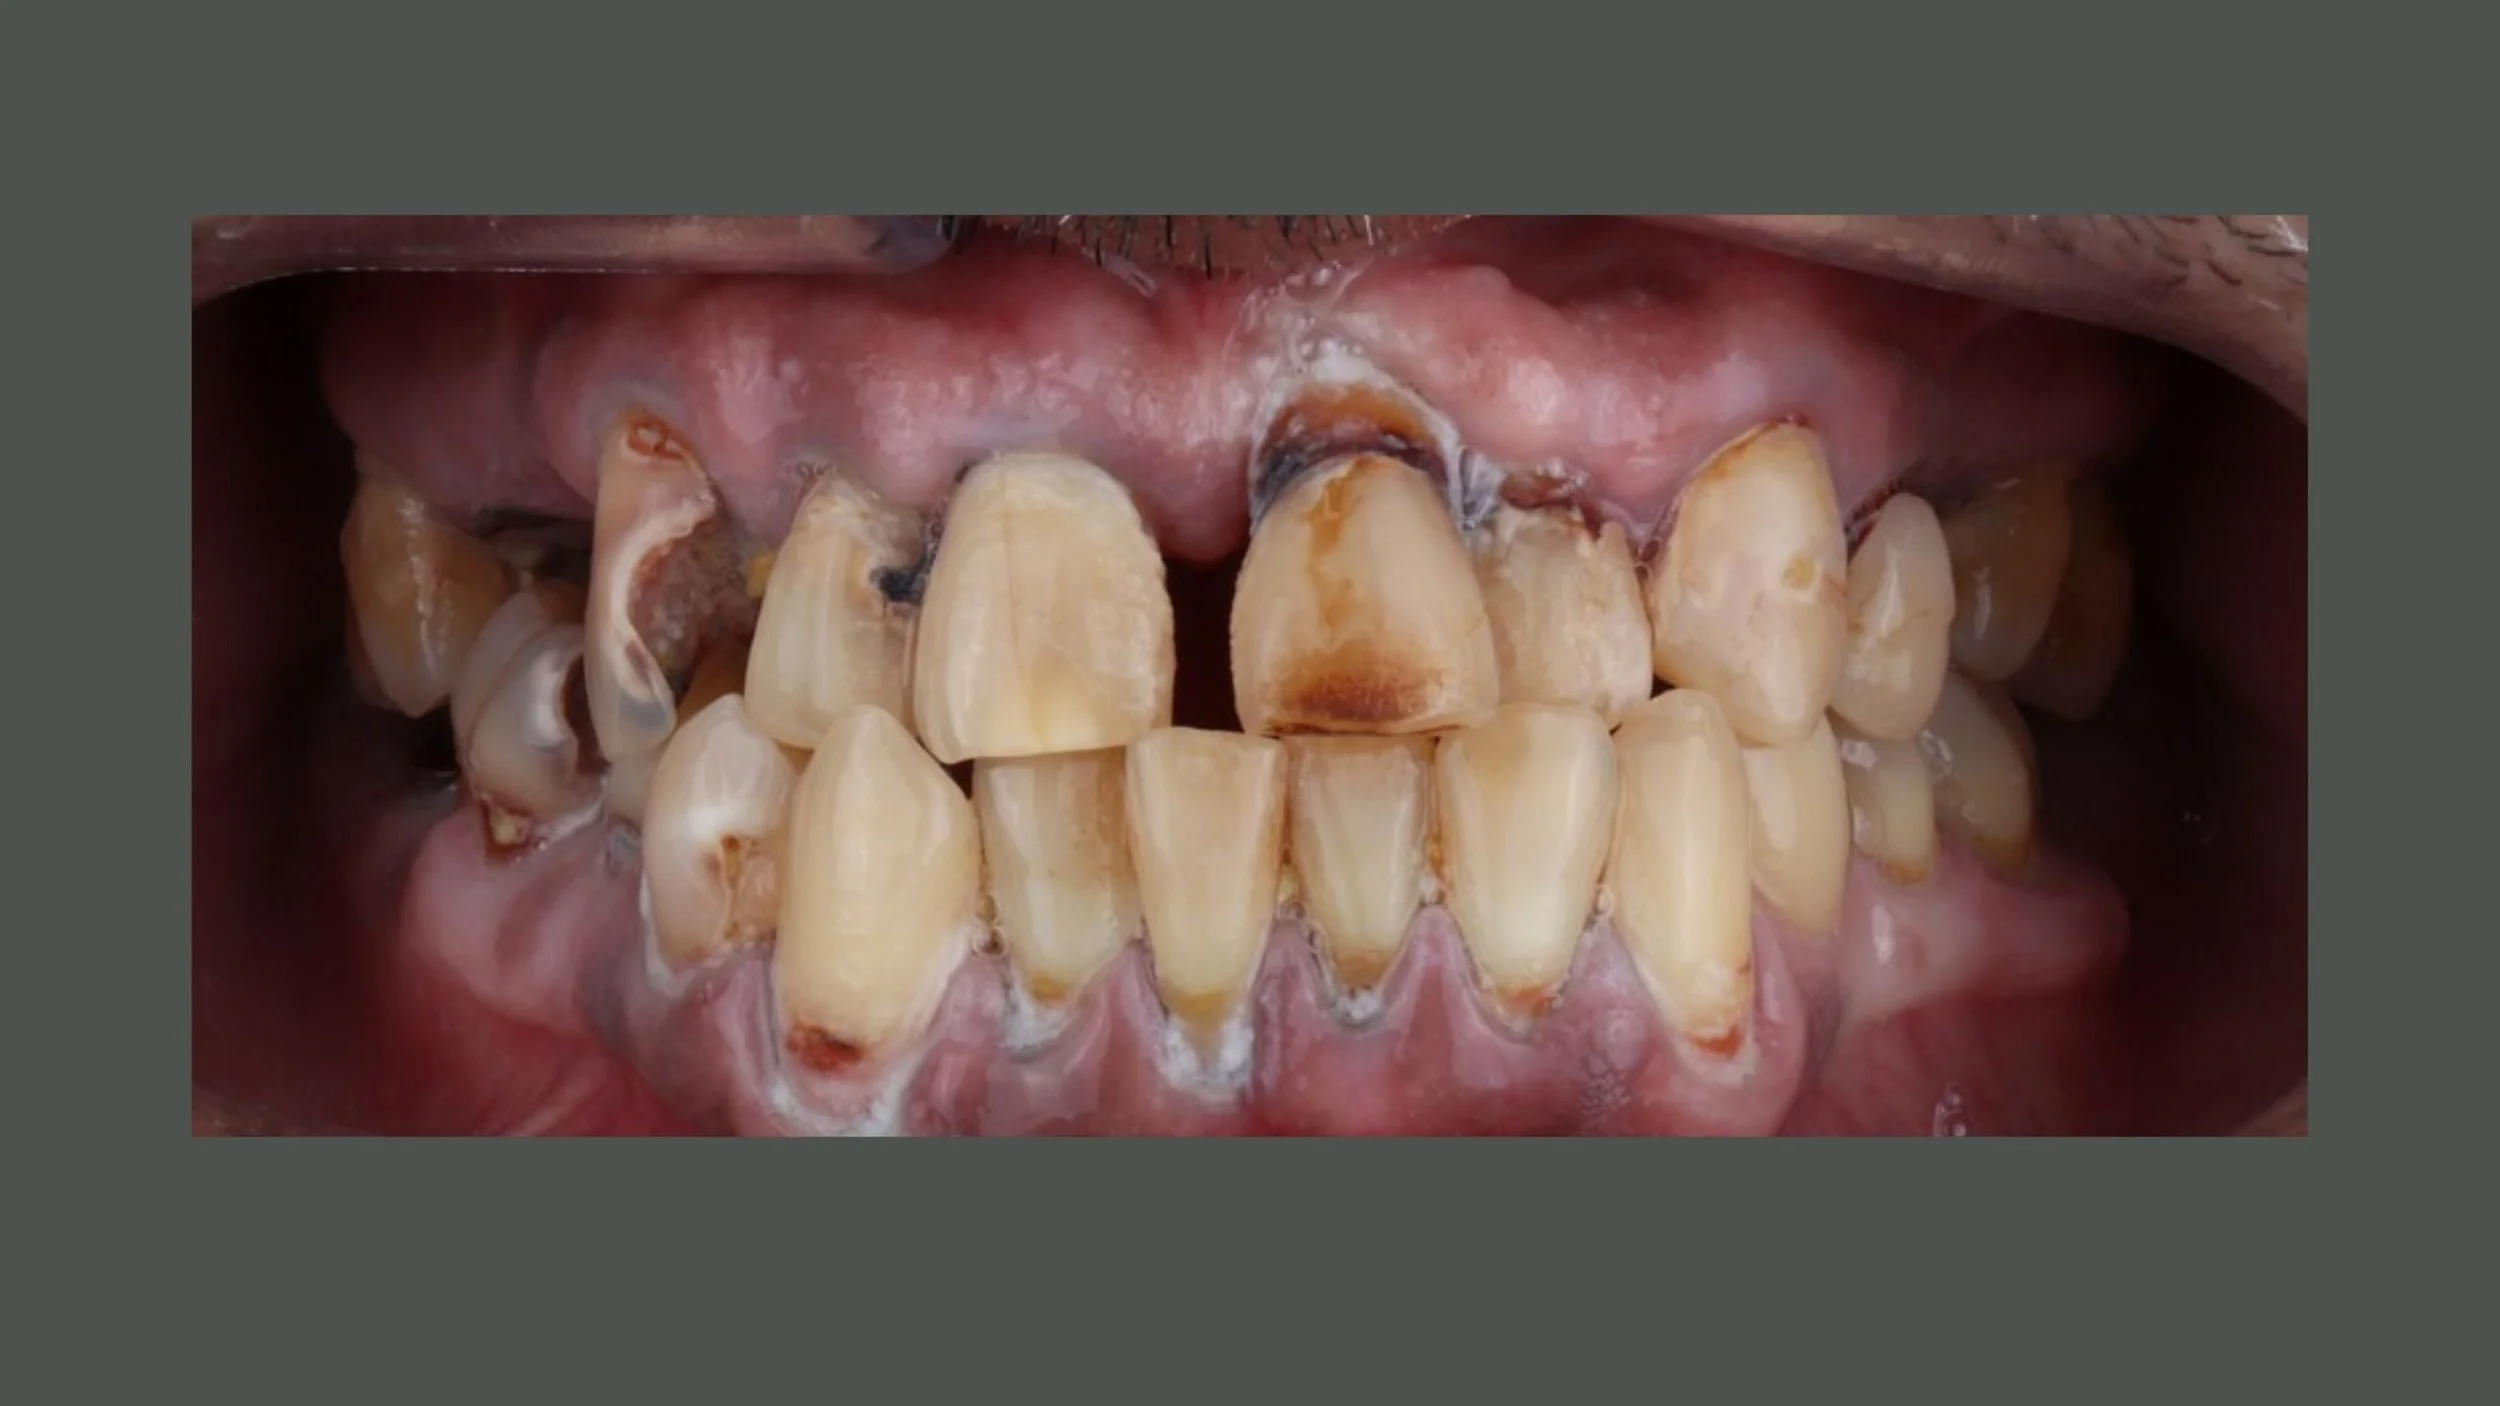

Full mouth rehabilitation can be 100% digital. From planning, to surgery, to final prosthetics.

Would you like to learn, how to do full mouth rehabilitation prosthetics without impression or photogrammetry and still achieve 100% passive fit? Just using intraoral scanner and CBCT.

Felix and Miguel have used this protocol over 10 years and can explain, how you can achieve the same result.

They currently have 93% success rate over the years. They have analyzed their failures and can give us understaning, what we need to to in order to avoid mistakes and achieve 99% success rate.

PROOF OF CONCEPT AND USABILITY

• Up to 10 years of follow-up data with this protocol

• 300 completed cases (93% prosthetic success rate 2017-2024 on 148 arches)

Medical case using R2GATE guided surgery and AnyRidge implants